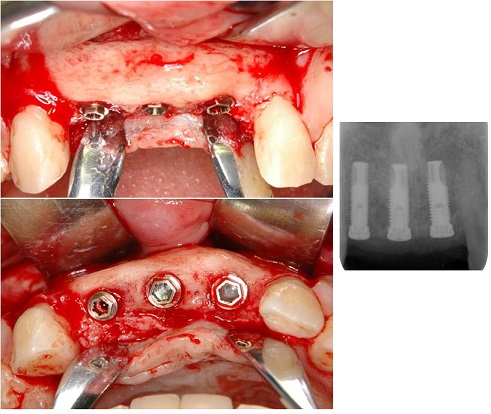

3.極度の骨・軟組織欠損がある2歯欠損症例(症例 5、自家骨移植と有茎口蓋弁移植)

極度の骨欠損があったが、オトガイ部から10mmの厚みの皮質海綿ブロック骨移植にて審美的インプラント治療を行いました。歯肉の厚みを増やすために有茎口蓋弁移植も併用しました。

4.極度の骨・軟組織欠損がある2歯欠損症例

(他院でトラブルとなった症例 2の再インプラント治療、自家骨移植と有茎口蓋弁移植)

まず予後不良インプラント撤去し、極度の骨欠損があったが、オトガイ部から10mmの厚みの皮質海綿ブロック骨移植にて審美的インプラント治療を行いました。歯肉の厚みを増やすために有茎口蓋弁移植も併用しました。